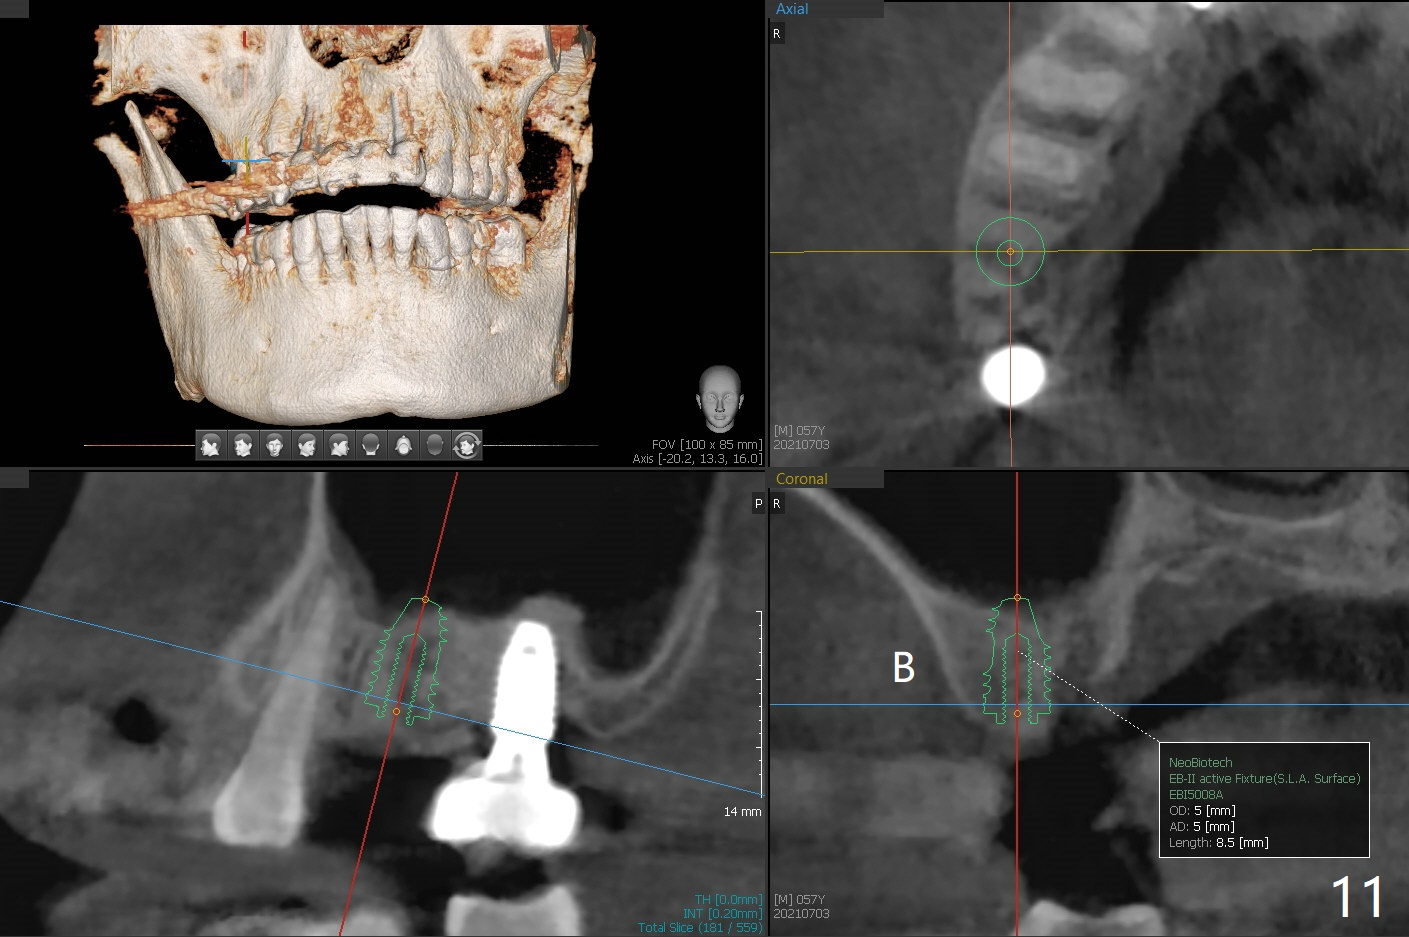

57岁男咬合力大,在右上7植体愈合中,6(3号牙)出现隐裂(图三),根管治疗后完全裂开(图四),需要拔除植骨。由于他特别害怕治疗,包括抽血,开始不想制作粘性骨块,但是考虑到我们最近用的皮质骨粉颗粒细,送到上颌磨牙牙槽窝困难,容易丢失,最后决定抽血提取上清液,制备粘性骨块(图五)。拔牙也有困难,虽然十分松动,但是无法脱位,研究两年前CT,牙根长,弯曲(图一,二),分根后才完成拔除,骨块剪成三块,分别插入三个牙槽窝(图六),覆盖PRF膜和压扁的胶原塞,缝合。术后一个月,角化龈基本保持原位。由于松弛缝合,角化龈有可能增加~6毫米(图七)。而且骨粉好像没有失去(图八,九 (P:腭侧;MB:近中颊侧;DB:远中颊侧))。术后十个月骨质高度降低(图十)。尤其是腭侧,所以植体需要偏向颊侧(图十一:B)。牙冠粘固后8个月,2号牙植体远中骨质吸收(图十二:<)。